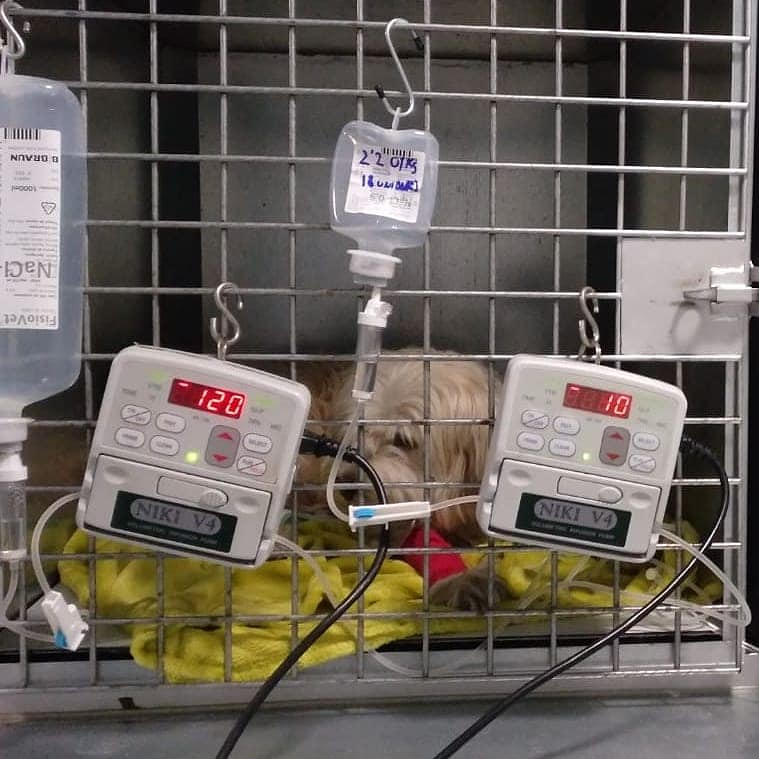

Hospitalizacion veterinaria

- Servicio de urgencias 24h